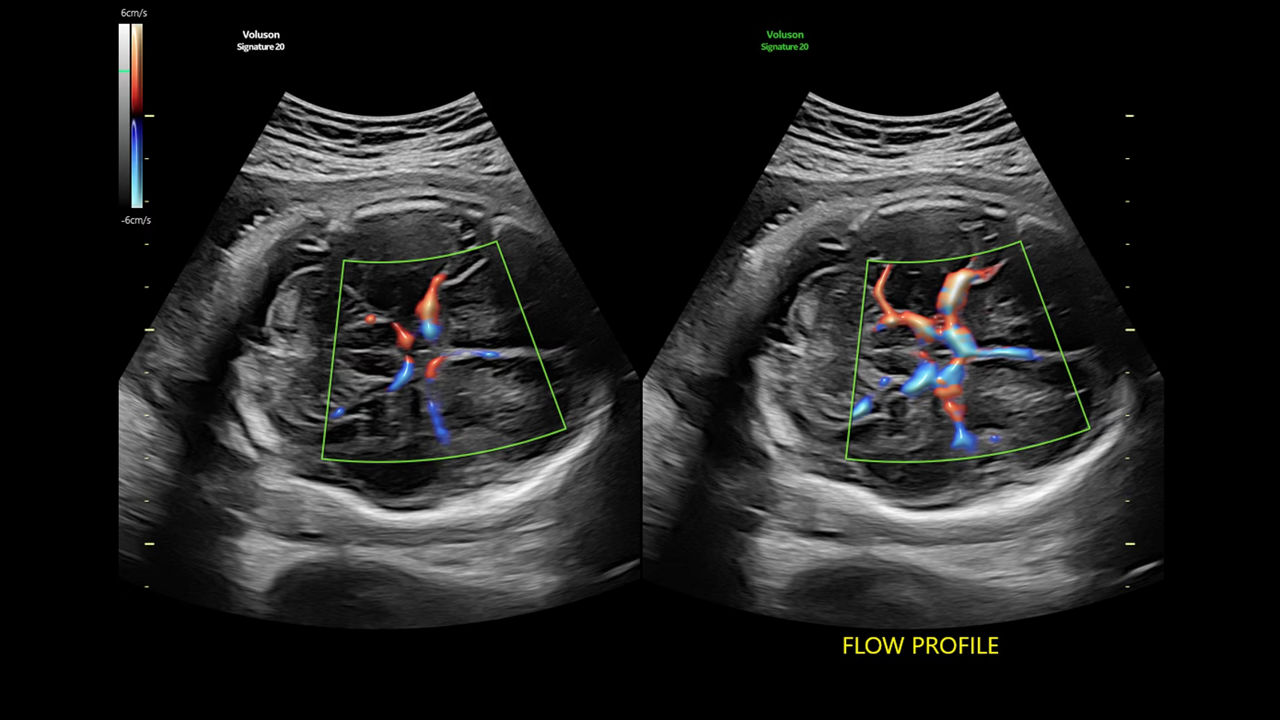

Reduce color and Doppler exam time by 56% with Flow Profiles

Next level color Doppler that delivers exceptional sensitivity for easy, fast visualization of blood flow, displaying a 3D like appearance as seen in this 27-week fetal heart.